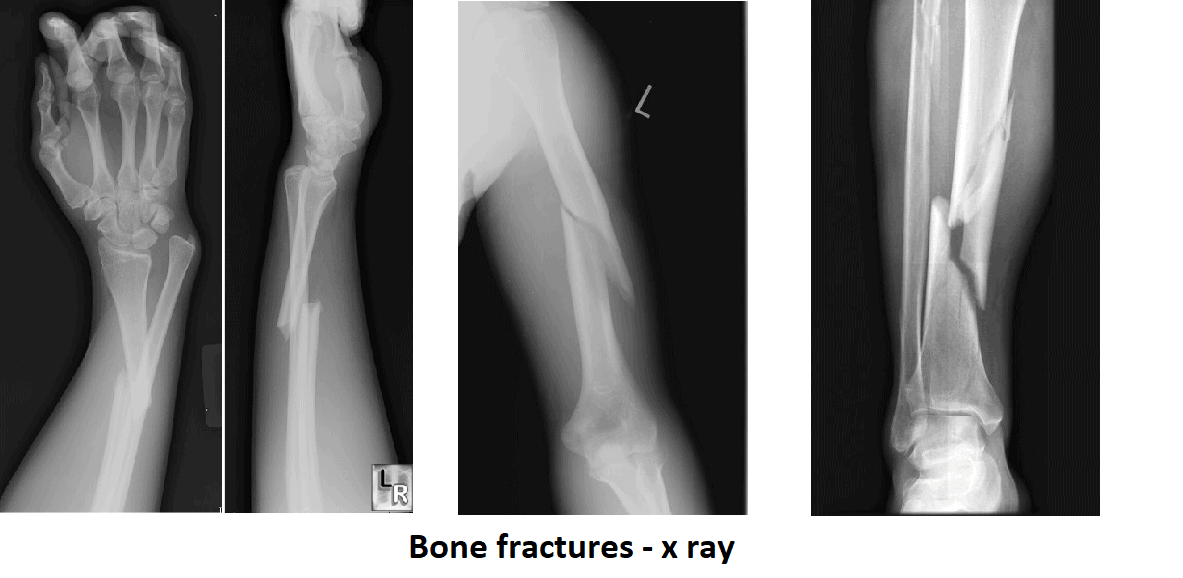

The best information about a bone fracture is given by radiographic diagnostics. X ray is done in two directions (anteroposteriorly and profile) and may also be in supplementary directions (oblique recording). Atlas General Hospital performs all the necessary X ray diagnostics in short period of time.